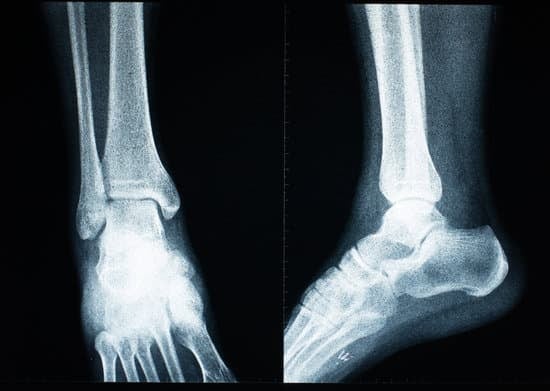

족관절 인공관절 치환술 (Total Ankle Replacement)

족관절(발목 관절)은 무릎과 발을 연결하며, 걷기, 달리기, 방향 전환 등 다양한 움직임을 담당하는 중요한 관절입니다.

하지만 관절염, 외상 후 관절 손상 등으로 인해 심한 통증과 운동 제한이 발생하면, 족관절 인공관절 치환술(Total Ankle Replacement)이 고려될 수 있습니다.

족관절 인공관절 치환술은 심하게 손상된 발목 관절을 제거하고,금속과 특수 재질의 인공관절로 대체하여 통증을 줄이고 움직임을 회복하는 수술입니다.

무릎이나 고관절의 인공관절 수술과 비슷한 원리로 진행되며,최근에는 인공관절 기술이 발전하면서 자연스러운 움직임과 기능 회복이 가능한 치료법으로 자리잡고 있습니다.